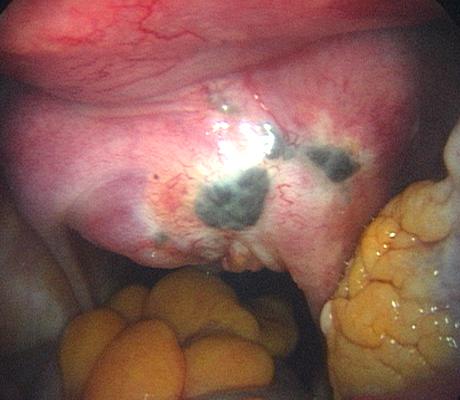

Endometriosis is a non-cancerous condition where the endometrial tissue or womb lining which normally grows only in the uterus is found in other parts of your pelvis, for example the ovaries, fallopian tubes, rectum, bladder, appendix and pelvic walls. This womb lining that grows outside the uterus responds also to hormones but at the time of your periods it can not be expelled (as the womb lining) and causes pain, cysts in the ovaries (called chocolate cysts), inflammation in your pelvis, scar tissue, pain with sexual intercourse, chronic pelvic pain, pain when passing bowel motions, lower backache, symptoms similar to urinary tract infections, premenstrual discomfort, etc.

Diagnosis of endometriosis can only be done with certainty through a laparoscopy. Although this means surgery, a patient can also be treated at the same time, saving an extra procedure and the associated risks.

Laparoscopy is an operation (keyhole surgery) conducted under general anaesthesia. A telescope is introduced into a small incision in your navel, other small incisions are made for using special laparoscopic instruments and all the pelvic organs are examined with magnification (Video-laparoscopy) ; then the endometriosis is treated. Video Laparoscopy allows conservative surgery (hysterectomy is NOT the usual treatment for endometriosis) which means laparoscopic excision of the endometriotic implants, with restoration of the normal anatomy and preservation of the uterus, tubes and ovaries.